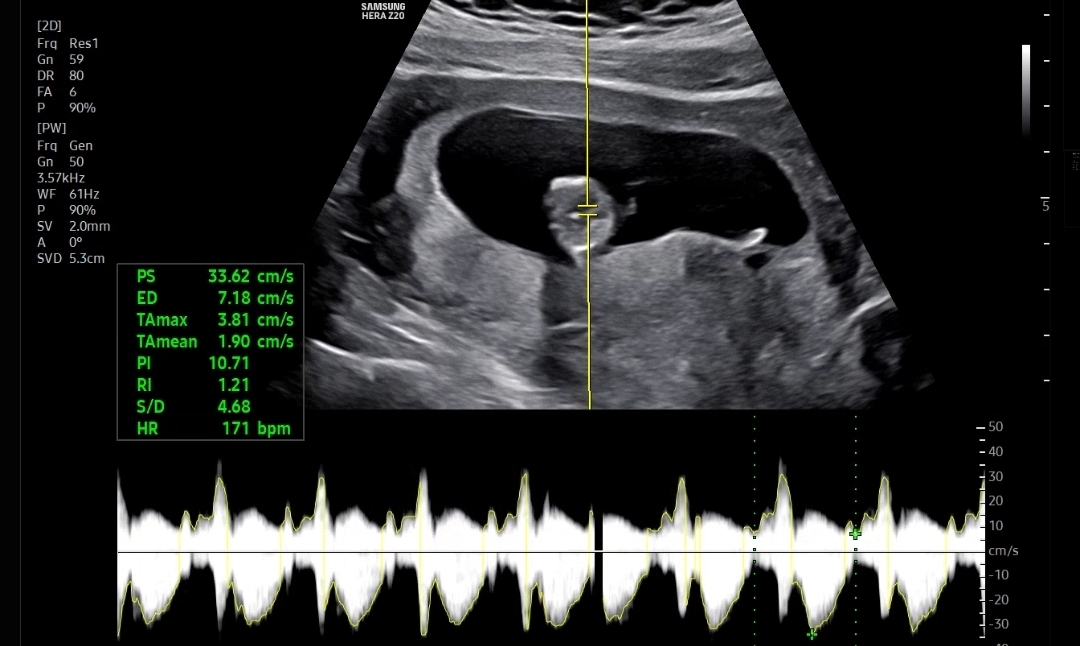

우선 아기크기와 심장소리를 확인했는데 아기크기도 6.26cm, 심장소리도 171bpm으로 잘 뛰고 있었다

마지막으로 확인한 콧대길이, 소뇌?길이, 목투명대 길이를 쟀다

코뼈길이는 0.26cm, 목투명대는 1.31mm 로 둘다 정상범위!

만약에 코뼈가 낮거나 목투명대가 3mm이상이면 다운증후군 위험이 있다고 했다